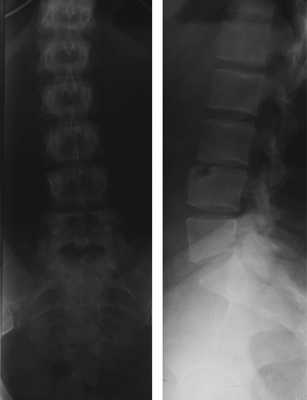

Рис.1 — Рентгенограмма поясничного отдела позвоночника (прямая и боковая проекции)

На рентгенограмме в боковой проекции визуализируется скошенный передний верхний угол тела L4 позвонка со смещенным костным фрагментом треугольной формы. Край фрагмента примерно соответствует размеру дефекта близлежащего позвонка.